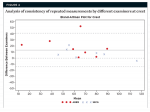

An analysis of internal consistency of repeated measurements by different examiners was accomplished by using the Bland-Altman plot, which is a visual representation of the differences between the two examiners. The intra-examiner measurements were more consistent than the interexaminer measurements. Crestal measurements by examiner 1 were typically higher than those of examiner 2 (Figure 4 through Figure 6).